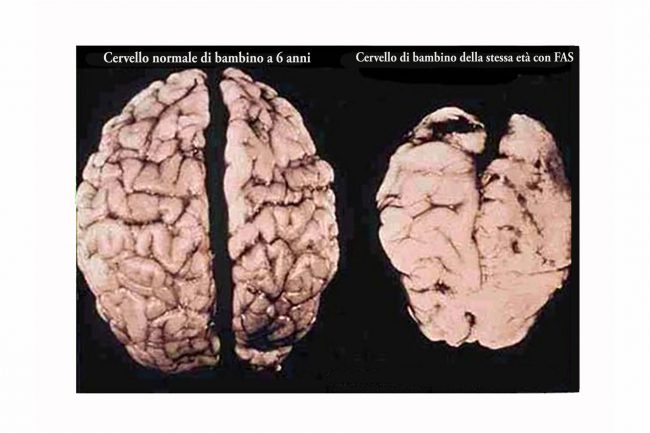

Oggi sappiamo che la sindrome alcolico fetale si traduce in:

dismorfologie facciali e i problemi cerebrali

alterato sviluppo del cranio

I dati epidemiologici dimostrano che, nonostante l’evidenza degli effetti dannosi correlati all’abuso di alcol, l’incidenza della FAS è in aumento. Questo è primariamente dovuto alla mancanza di un’adeguata consapevolezza nell’opinione pubblica, che tende ad associare il problema della FAS all’assunzione di bevande superalcoliche, sebbene possa risultare pericolosa per il feto anche una moderata assunzione di birra e di vino. Questo perché i tempi di eliminazione dell’alcol, già lunghi nella donna (che ha una minore capacità di metabolizzare le bevande alcoliche rispetto all’uomo), sono per il feto ancora più dilatati. Se una donna incinta consuma bevande alcoliche, l’alcol e, soprattutto, l’acetaldeide (prodotto della metabolizzazione dell’alcol) giunge direttamente nel sangue del nascituro attraverso la placenta. Il feto non essendo in grado di metabolizzare l’alcol come un adulto, viene di conseguenza esposto più a lungo ai suoi effetti nocivi.